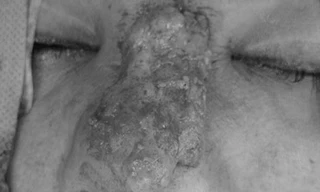

Hiện nay, nhiều người vẫn chưa thật sự hiểu việc tiêm chất làm đầy dỏm, không rõ nguồn gốc cũng giống như tiêm ung thư vào người. Chị T.H.C, 38 tuổi, ngụ tại Vũng Tàu đã phải gánh chịu chịu hậu quả sau khi nâng mũi bằng cách tiêm chất làm đầy không rõ nguồn gốc.